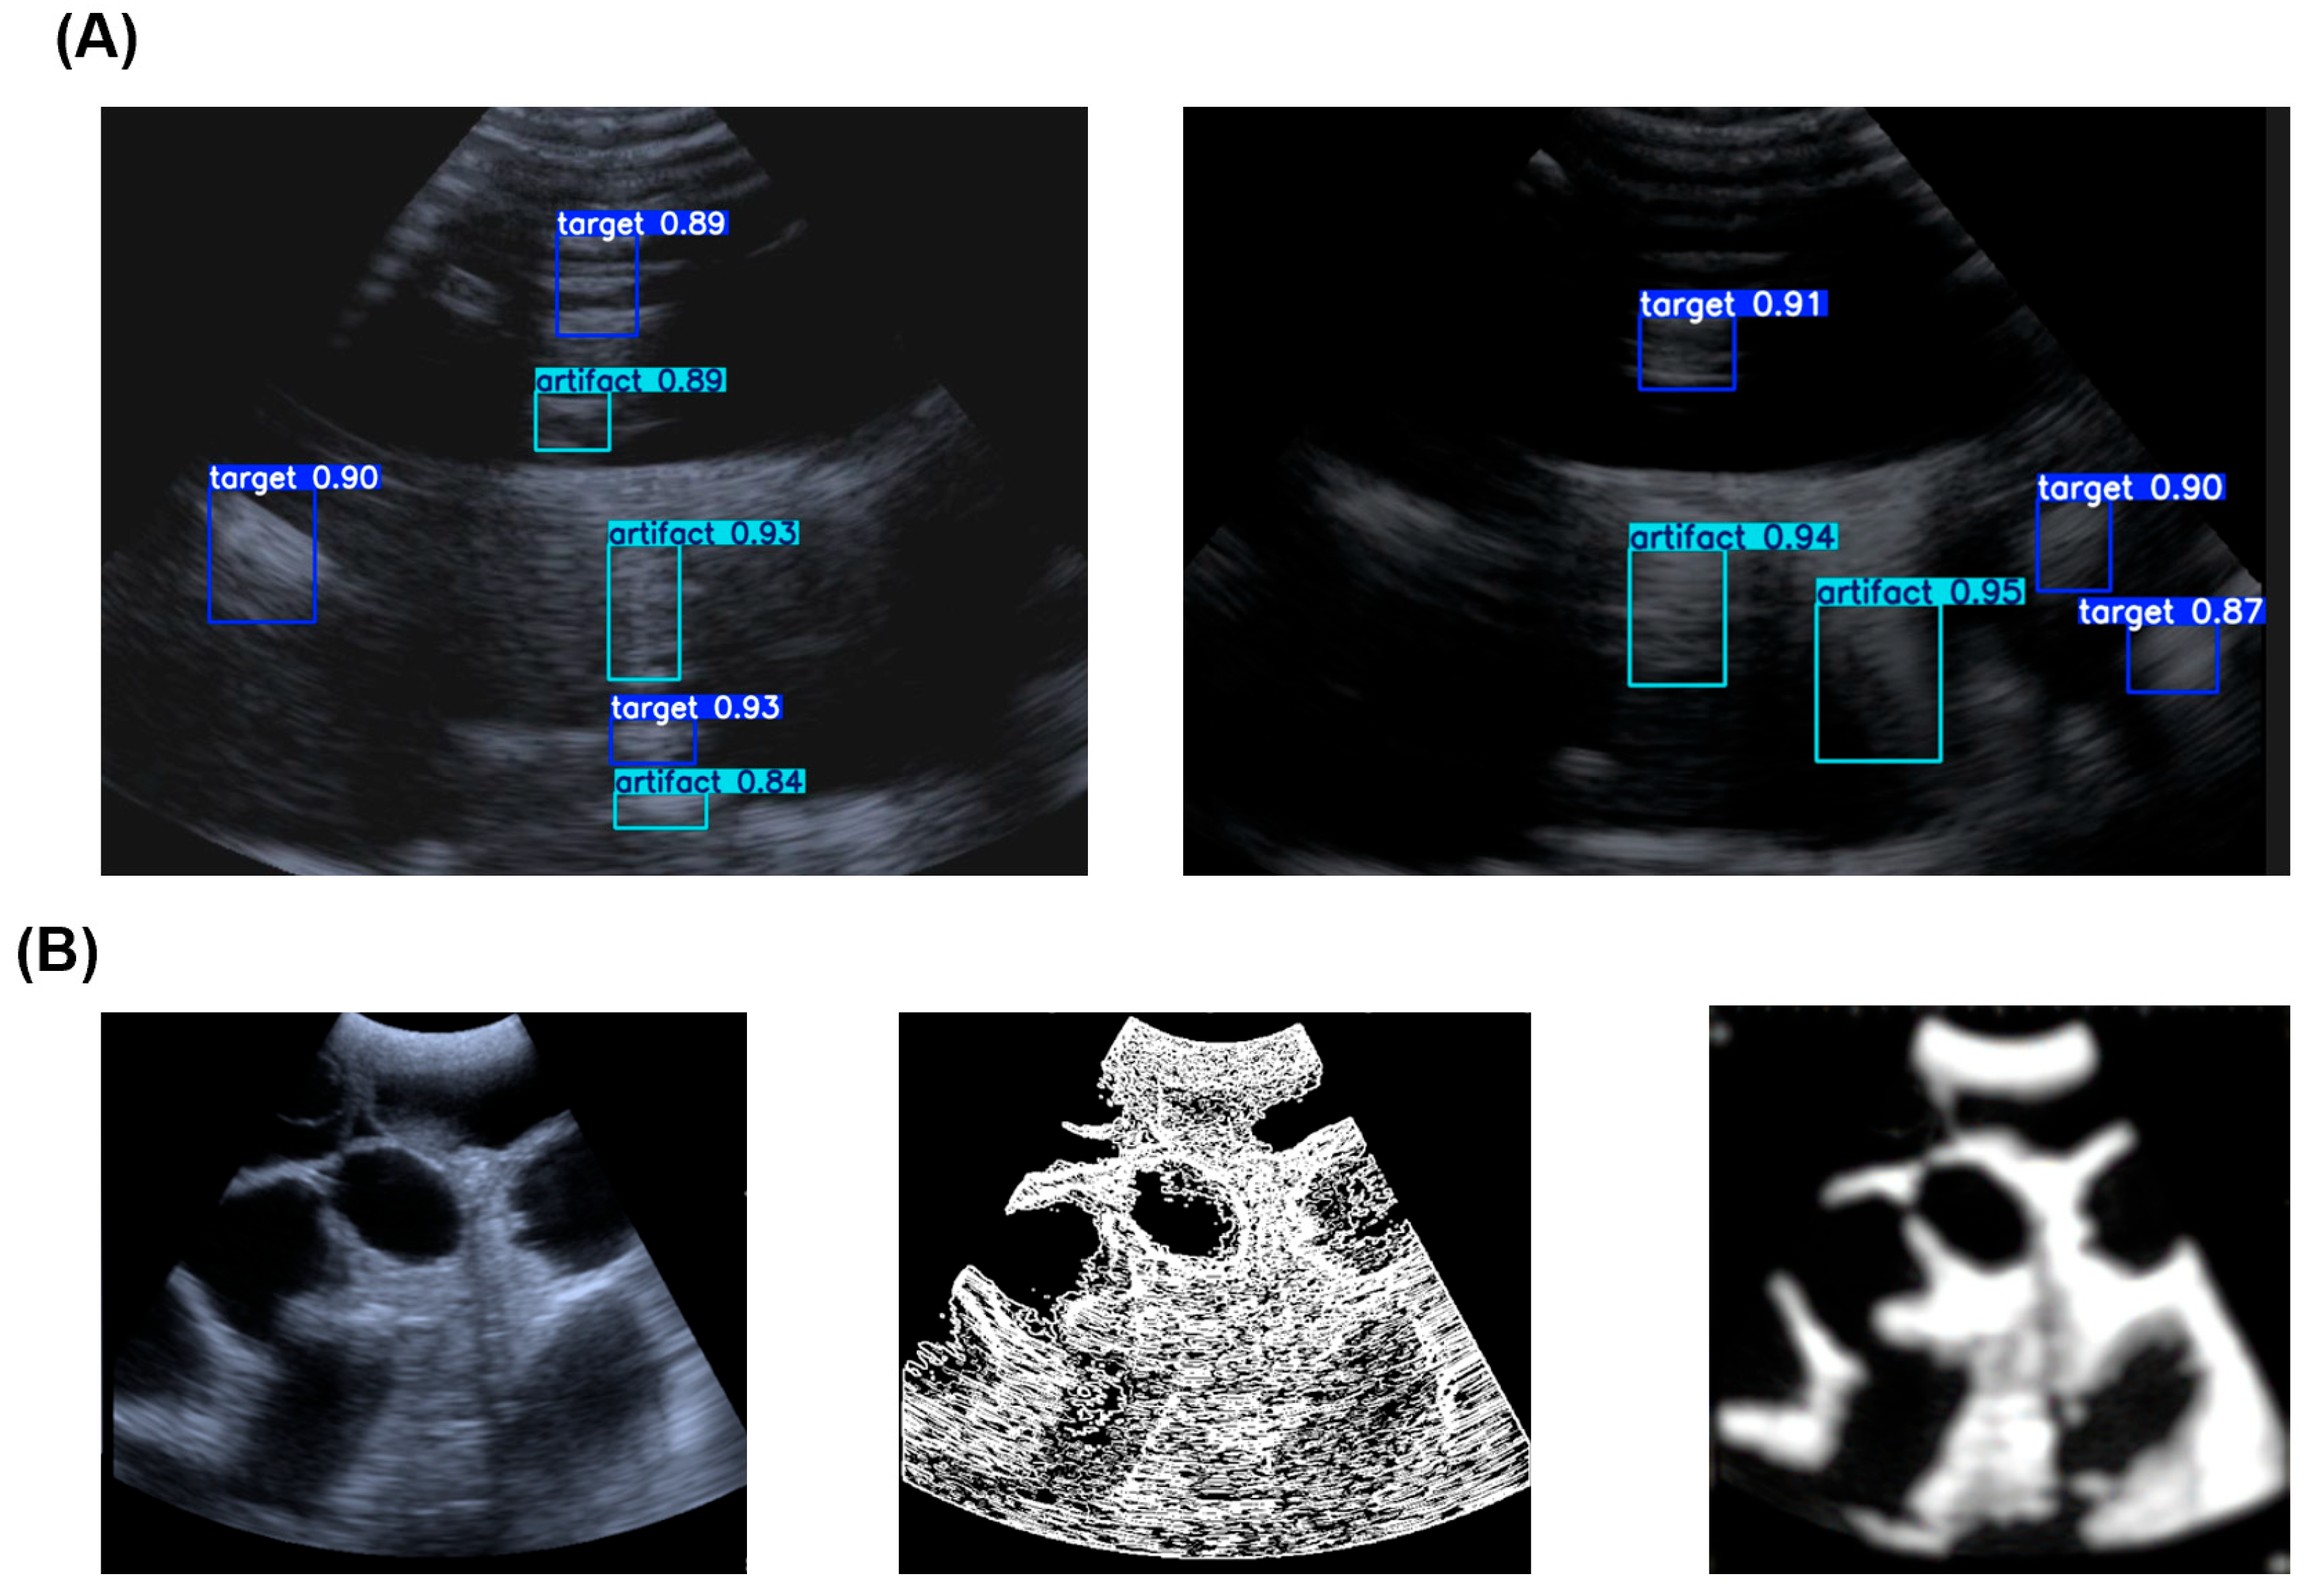

2. Experimental Section: System and Principles

3. AI Algorithm for Biosensor Signal Enhancement

3.1. Dataset Construction and Enhancement for Robust Training

3.3. Error Analysis and Evaluation of Image Enhancement